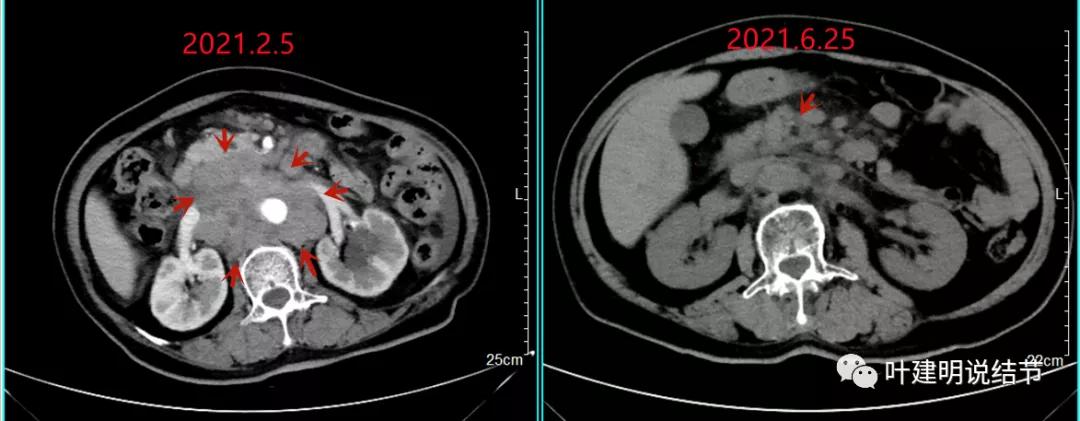

上图同样左侧是治疗前的,右侧经过2周期免疫加化疗后复查的,可见病灶缩小甚至超过9成。下面是治疗前与后来于6月底复查的: